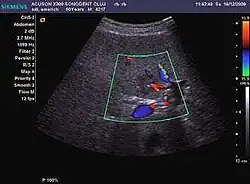

It is a tumor developed secondary to a circulatory abnormality with abundant arterial vessels having a characteristic location in the center of the tumor, within a fibrotic scar. A radial vessels network develops from this level with peripheral orientation. The tumor's circulatory bed is rich in microcirculatory and portal venous elements. The incidence is higher in younger women and tumor development is accelerated by oral contraceptives intake. 2D ultrasound appearance is a fairly well-defined mass, with variable sizes, usually single, solid consistency with inhomogeneous structure. Rarely the central scar can be distinguished. Spectral Doppler examination detects central arterial vessels and CFM exploration reveals their radial position. CEUS examination shows central tumor filling of the circulatory bed during arterial phase and completely enhancement during portal venous phase. During this phase the center of the lesion becomes hypoechoic, enhancing the tumor scar. During the late phase the tumor remains isoechoic to the liver, which strengthens the diagnosis of benign lesion.

HCC appearance on 2D ultrasound is that of a solid tumor, with imprecise delineation, with heterogeneous structure, uni- or multilocular (encephaloid form). An "infiltrative" type is also described which is difficult to discriminate from liver nodular reconstruction in cirrhosis. Typically HCC invades liver vessels, primarily the portal veins but also the hepatic veins . Doppler examination detects a high speed arterial flow and low impedance index (correlated with described changes in tumor angiogenesis). The spatial distribution of the vessels is irregular, disordered. CEUS examination shows hyperenhancement of the lesion during the arterial phase. During the portal venous phase there is a specific "wash out" of ultrasound contrast agent (UCA) and the tumor appears hypoechoic during the late phase. Poorly differentiated tumors may have a stronger wash out leading to an isoechoic appearance to the liver parenchyma during portal venous phase. This appearance was found in approx. 30% of cases. The described changes have diagnostic value in liver nodules larger than 2 cm.